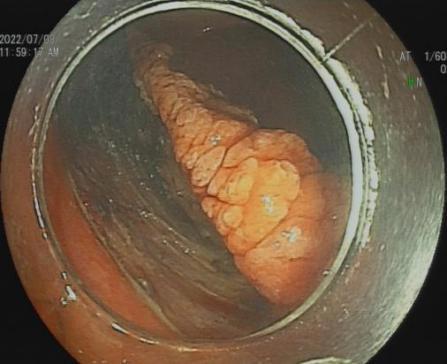

三、早期消化道肿瘤ESD技术

内镜下粘膜剥离术(ESD),具有超级微创、安全性高、住院时间短及费用低等优势。

直肠巨大绒毛状腺瘤 内镜下粘膜剥离过程

粘膜剥离术后创面 剥离的巨大腺瘤